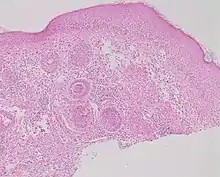

Rosacea on the face

Micrograph showing rosacea as enlarged, dilated capillaries and venules located in the upper dermis, angulated telangiectasias, perivascular and perifollicular lymphocytic infiltration, and superficial dermal edema.[18]